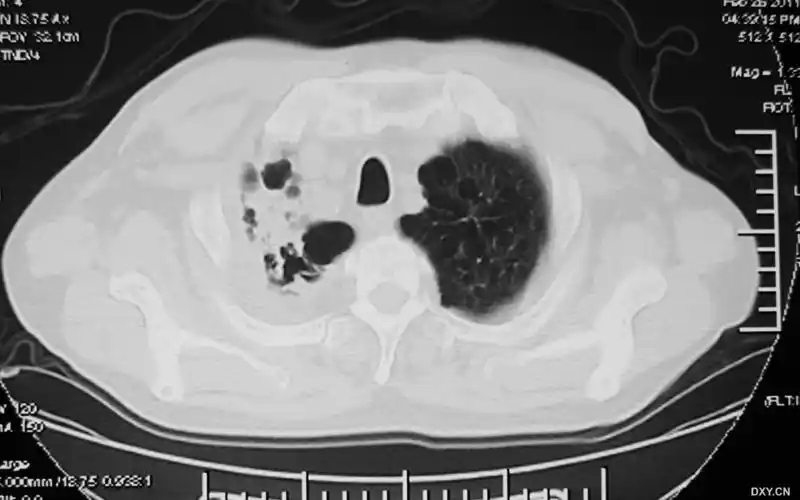

有慢性支气管炎十余年,肺气肿9年.增加了新图像资料,以作对比.